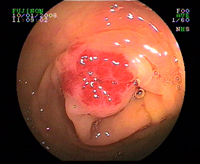

Cancer du colon

Cancer du rectum